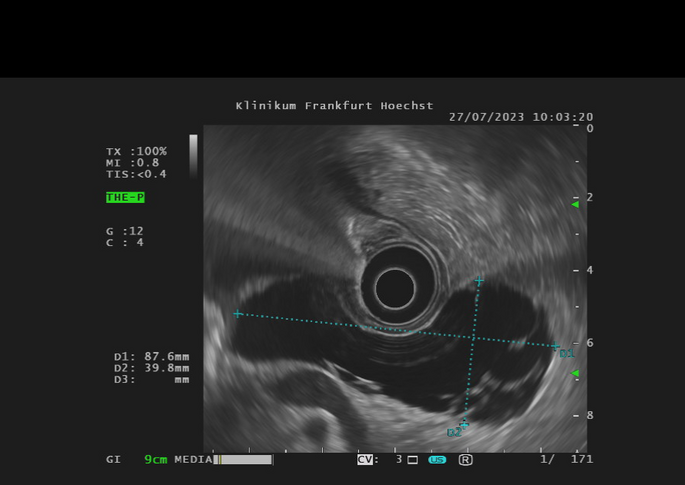

Die Endosonographie ermöglicht eine sehr schonende Diagnostik und Therapie an den Bauchorganen. Im Vergleich zu anderen bildgebenden Verfahren wie der Abdomensonographie, der Computertomographie (CT) oder der Magnetresonanztomographie (MRT) bietet nur die Endosonographie den Blick von innen auf die Organe. Die Speiseröhre (Ösophagus), Magen, Zwölffingerdarm (Duodenum), Bauchspeicheldrüse (Pankreas), Gallenwege, Gallenblase und Enddarm (Rektum) liegen besonders im Fokus der Endosonographie.

Aber auch bei der Gewinnung von Gewebeproben auf möglichst schonendem Wege kommt die Endosonographie zum Einsatz. Hierbei werden Proben z.B. aus dem Pankreas, Lymphknoten oder anderweitigen Befunden entnommen (endosonographische Punktion, endosonographische Feinnadelaspiration). Neuere Techniken umfassen die Therapie von Gallenblasenentzündungen (endosonographische Gallenblasendrainage)  und die Wiederherstellung der Nahrungspassage bei Verlegungen im Magen-Darm-Trakt (endosonographische Gastroenterostomie).